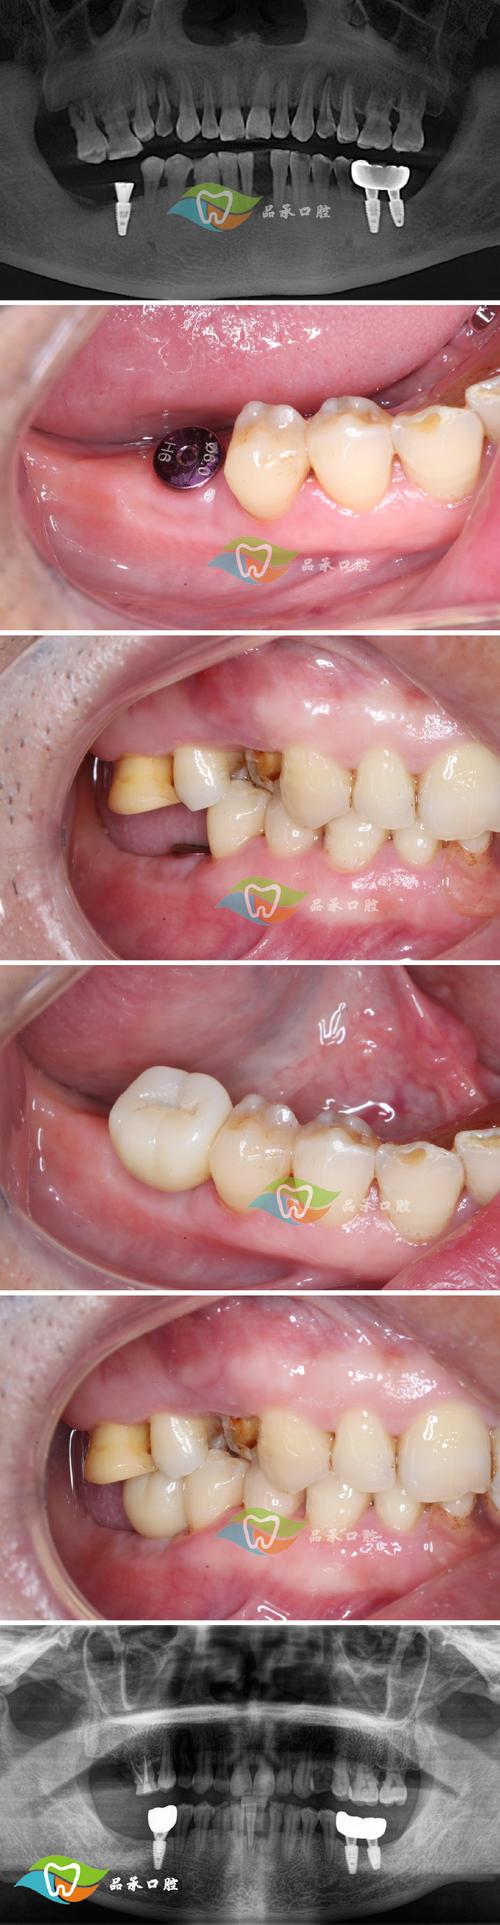

当植骨区骨结合良好(影像学显示骨密度均匀、植骨材料与自体骨界限模糊),医生会进行种植体植入手术,进入负重使用期,此时种植体通过“骨结合”与新生骨组织牢固结合,上部修复体(牙冠)恢复咀嚼功能,但长期维护仍至关重要,以确保种植牙使用寿命。

恢复特点:种植体植入后,通常需3-6个月的二次骨结合(与植骨区骨融合),之后安装牙冠,进入功能使用阶段,初期使用时,种植牙可能轻微松动或异物感(正常现象),1-2周后逐渐适应;咀嚼功能从软食过渡到正常饮食,但需避免咬硬物(如开酒瓶、咬核桃),防止种植体或牙冠损坏。